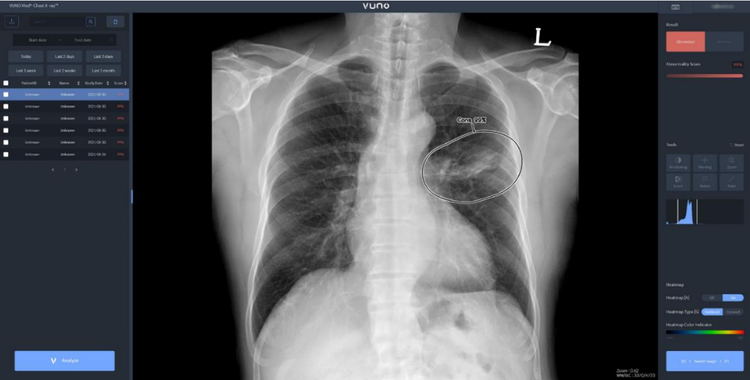

이번 태국 허가를 획득한 뷰노메드 체스트 엑스레이™는 흉부 엑스레이 영상에서 결절, 경화, 간질성 음영, 흉수, 기흉 등 주요 이상소견을 높은 정확도로 탐지하는 인공지능 솔루션이다. 의료진에게 이상소견의 소견명과 위치를 제시해 결핵, 폐렴 등 주요 폐 질환 진단을 돕는다.

해당 솔루션은 영상의학 분야 최고 권위 학술지인 Radiology에 게재된 임상연구에서 높은 판독 정확도와 효율성을 입증한 바 있다. 국내외 주요 중대형병원에서 활발하게 사용되며 임상적 가치가 검증된 주요 제품 중 하나다.